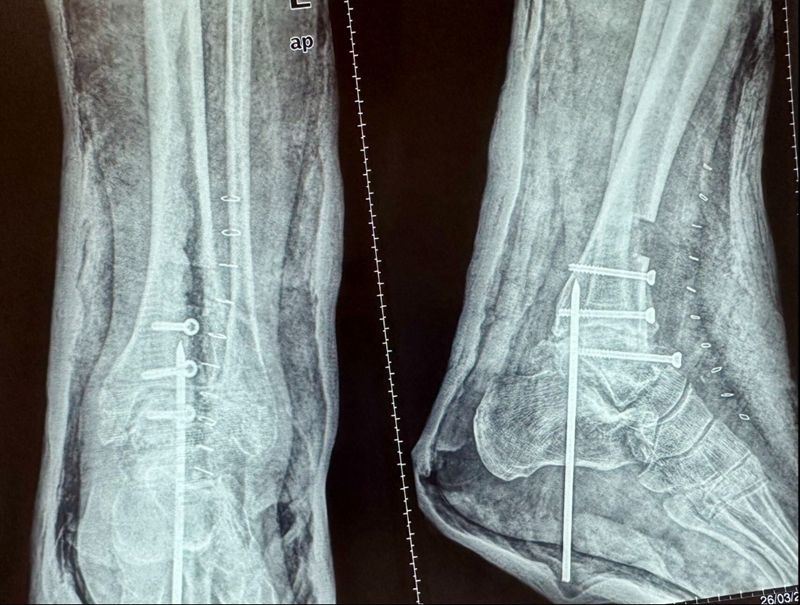

图23 手术后资料

病例报告之二,xx,男,56岁,左踝创伤性关节炎。左踝崴伤6年,疼痛加剧3年。切口显露同前。